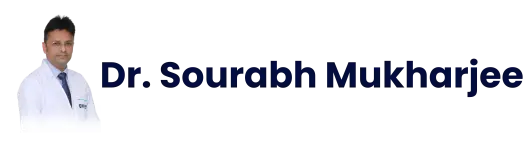

Understanding the Esophagus and Esophageal Cancer

The esophagus is a hollow, muscular organ approximately 25 cm long that connects the throat (pharynx) to the stomach. Its primary function is to transport food through coordinated muscular contractions known as peristalsis.

Esophageal cancer develops when abnormal cells in the lining of the esophagus begin to grow uncontrollably. Over time, these cells can invade deeper layers of the esophageal wall and spread to nearby lymph nodes or distant organs.

Types of Esophageal Cancer

There are two main histological types of esophageal cancer: